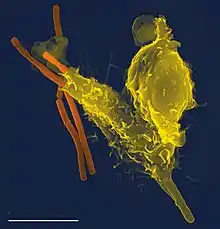

Under en infektion tiltrækkes fagocytter af kemiske signaler til steder, hvor patogenet har invaderet kroppen. Disse kemiske signaler kan komme fra bakterier eller fra andre fagocytter, der allerede er til stede. Denne metode at bevæge sig på kaldes kemotaksi. Når en fagocyt kommer i kontakt med en bakterie, vil receptorerne på fagocytens overflade binde sig til den, og bindingen vil medføre at fagocytten opsluger bakterierne. Denne proces kaldes fagocytose. Nogle fagocytter dræber det indtagne patogen med oxidanter og nitrogenoxid. Efter fagocytosen kan makrofager og dendritiske celler også deltage i antigenpræsentationen, en proces, hvor en fagocyt flytter molekylære brudstykker af det indtagne materiale tilbage på overfladen. Dette materiale vises derefter til andre celler i immunsystemet. Nogle fagocytter lokaliseres derefter til kroppens lymfeknuder og viser materialet til hvide blodlegemer kaldet lymfocytter. Disse processer er vigtig for at opbygge kroppens immunitet, jvf. immunsystemet.